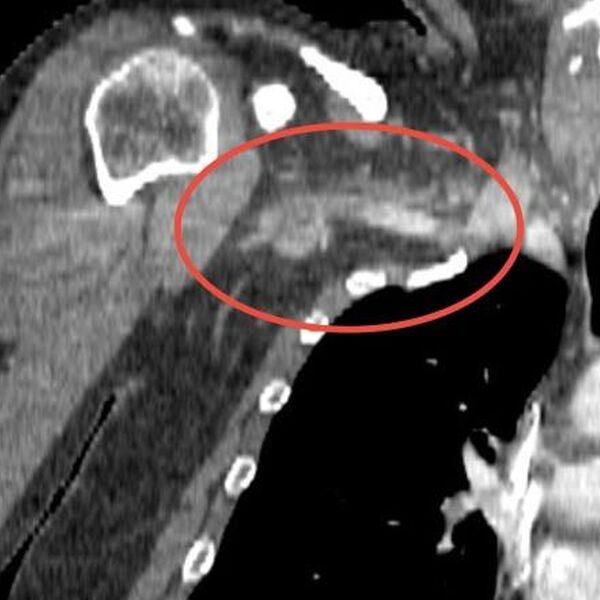

Врачи Долгопрудненской больницы спасли 34-летнего мужчину, у которого сосуды от плеча до шеи закупорил гигантский тромб. Об этом сообщили в пресс-службе Минздрава Московской области.

Во время диагностики медики установили, что в части сосудов у мужчины полностью отсутствует кровоток.

«Причиной артериального тромбоза оказался огромный 25-сантиметровый сгусток тромболитической массы, закупоривший сосуды от плеча до шеи. <…> В ходе 1,5-часовой операции мы удалили тромб с помощью специального баллона, который, расправившись, контролируемо продвинул сгусток далее по сосуду к разрезу в районе локтевого сгиба. Там мы зацепили его специальным крючком и благополучно извлекли», — поделился сосудистый хирург больницы Михаил Пырля.

Врач отметил, что в случае бездействия мужчина мог лишиться конечности. А в случае попадания части тромба в мозг последствия могли быть непоправимыми.